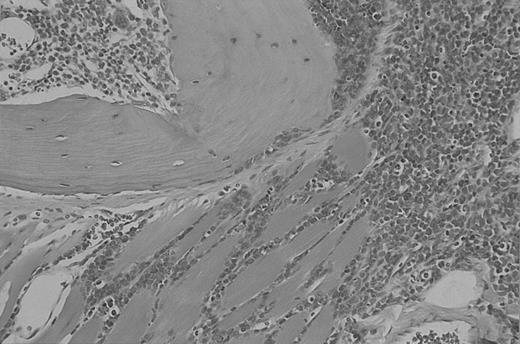

Animals of other p190 del C transgenic lines, including nos. 4231 and 4243, also developed leukemia/lymphoma, albeit sporadically. For example, animal no. 5085, a descendant of F0 no. 4243 (Table 1), developed lymphoblastic lymphoma/leukemia with lymph node and splenic involvement. There was no hepatomegaly or splenomegaly. Its pleural cavity contained a cellular exudate consisting of lymphoblasts. The bone marrow of this animal contained malignant lymphoblasts that invaded the surrounding muscle (Figure5).

Involved bone marrow of mouse no. 5085 (p190 del C no. 4243 line).

Magnification × 20. Tissues were stained with hematoxylin-eosin stain.